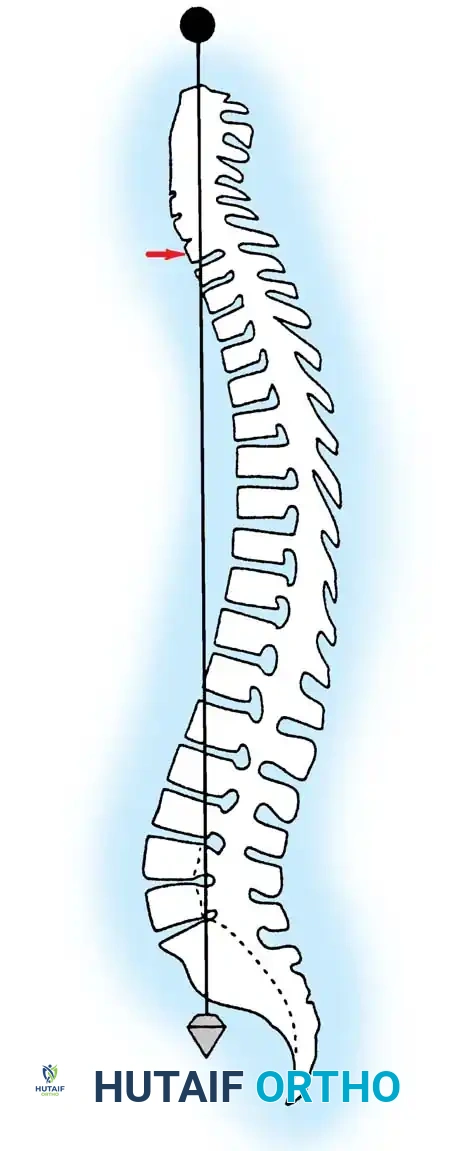

Normal sagittal balance is clinically defined by a plumb line dropped from the center of the C7 vertebral body, which should intersect the posterior superior corner of the S1 vertebra.

Positive sagittal balance occurs when the sagittal vertical axis (SVA) plumb line falls anterior to the sacrum, whereas negative sagittal balance occurs when the plumb line falls posterior to the sacrum. In the upright position, the spine is continuously subjected to gravitational forces. Several anatomical structures act in concert to maintain stability: the intervertebral disc complex (nucleus pulposus and anulus fibrosus), the ligamentous restraints (anterior longitudinal ligament, posterior longitudinal ligament, ligamentum flavum, apophyseal joint capsules, and interspinous ligaments), and the dynamic muscular envelope (long spinal erectors, short intrinsic rotatores/multifidi, and the abdominal musculature).